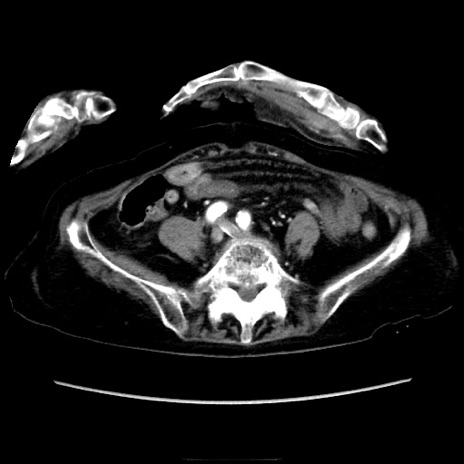

症例40(横断像)

【症例】90歳代女性

【主訴】腹痛・嘔吐

【現病歴】 食欲低下、嘔吐があり昨日他院受診。肺炎と診断され入院となる。入院後より腹部全体に圧痛あり。胃管留置され経過みていたが、症状持続するため、

当院転院となる。

【既往歴】胸椎圧迫骨折、胆石症

【身体所見】腹部:中央に激痛あり、圧痛あり、反跳痛不明

【データ】WBC 17100、CRP 18.82

横断像